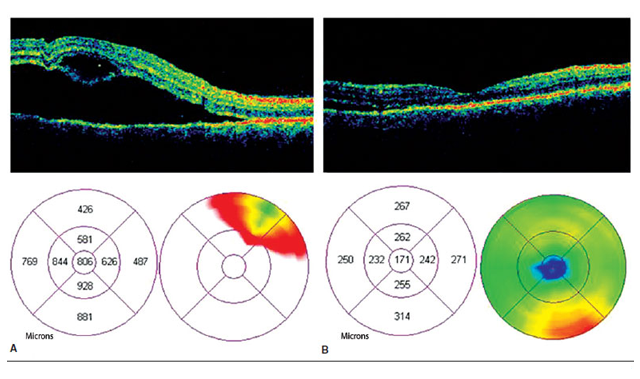

A tomografia de coerência óptica é um exame da visão que nos permite avaliar a retina com um raio de luz fazendo um corte quase anatômico de suas estruturas e que nos permite avaliar as diferentes camadas da retina, facilitando o diagnostico de doenças na mácula, pólo posterior de retina e o disco óptico, observando as diferentes características de estas estruturas como espessura, a presença ou ausência de continuidade das camadas, acumulo de liquido e formação de cistos comprometendo o bom funcionamento de retina. Ajuda no diagnostico e acompanhamento de doenças da retina e o glaucoma.

É possível fazer análise de progressão do glaucoma e auxiliar no diagnóstico precoce da doença.